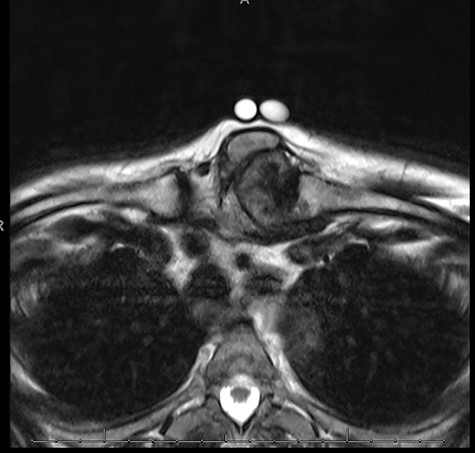

Both magnetic resonance imaging (MRI) and computed tomography (CT) scanning demonstrated a lobulated calcified and necrotic mass of 3.9 cm by 4.3 cm on the left SCJ causing a mass effect on adjacent structures (Fig. 1). Anteriorly the mass was bordered by the sternocleidomastoid muscle and dorsally by the sternohyoid muscle. There was compression of the left hemi-thyroid causing displacement of the trachea. There was no direct contact with the aorta or brachiocephalic vein.

MRI sternoclavicular joint showing lobulated calcified and necrotic mass of 3.9 cm by 4.3 cm on the left SCJ causing a mass effect on adjacent structures; anteriorly the mass is bordered by the sternocleidomastoid muscle and dorsally by the sternohyoid muscle.